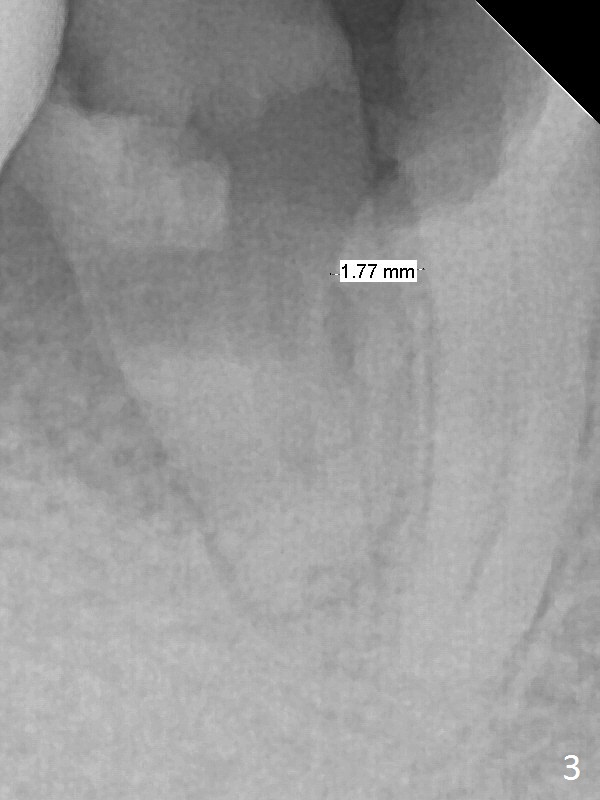

A 43-year-old man has residual roots at #30 (Fig.1). The mesial (M) and distal (D) roots approximates each other so close that the septum is thin (Fig.1,3-5). The latter is unfavorable for osteotomy. After extraction (Fig.5), the middle of the septum (Fig.8a (axial section of the sockets)) will be sectioned (Fig.6, 8b,c) prior to initial osteotomy (Fig.7,8d). The depth of the latter will be ~ 5 mm (Fig.2 red line) for a 13 mm (pink line) IBS implant.